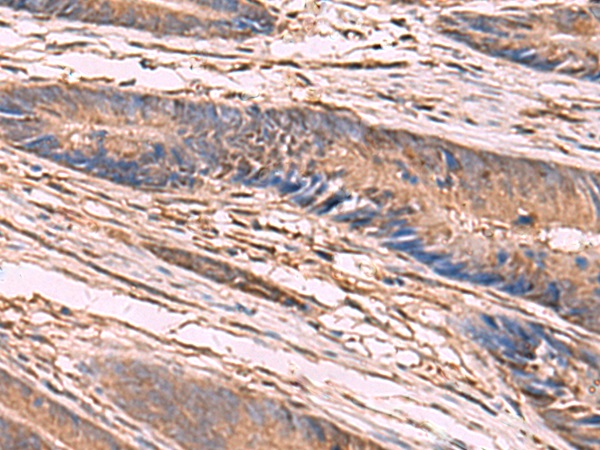

图片:

The image is immunohistochemistry of paraffin-embedded Human liver cancer tissue using 47688(KCNN2 Antibody) at dilution 1/65.(Original magnification: 200)

,

The image is immunohistochemistry of paraffin-embedded Human colorectal cancer tissue using 47688(KCNN2 Antibody) at dilution 1/65.(Original magnification: 200)